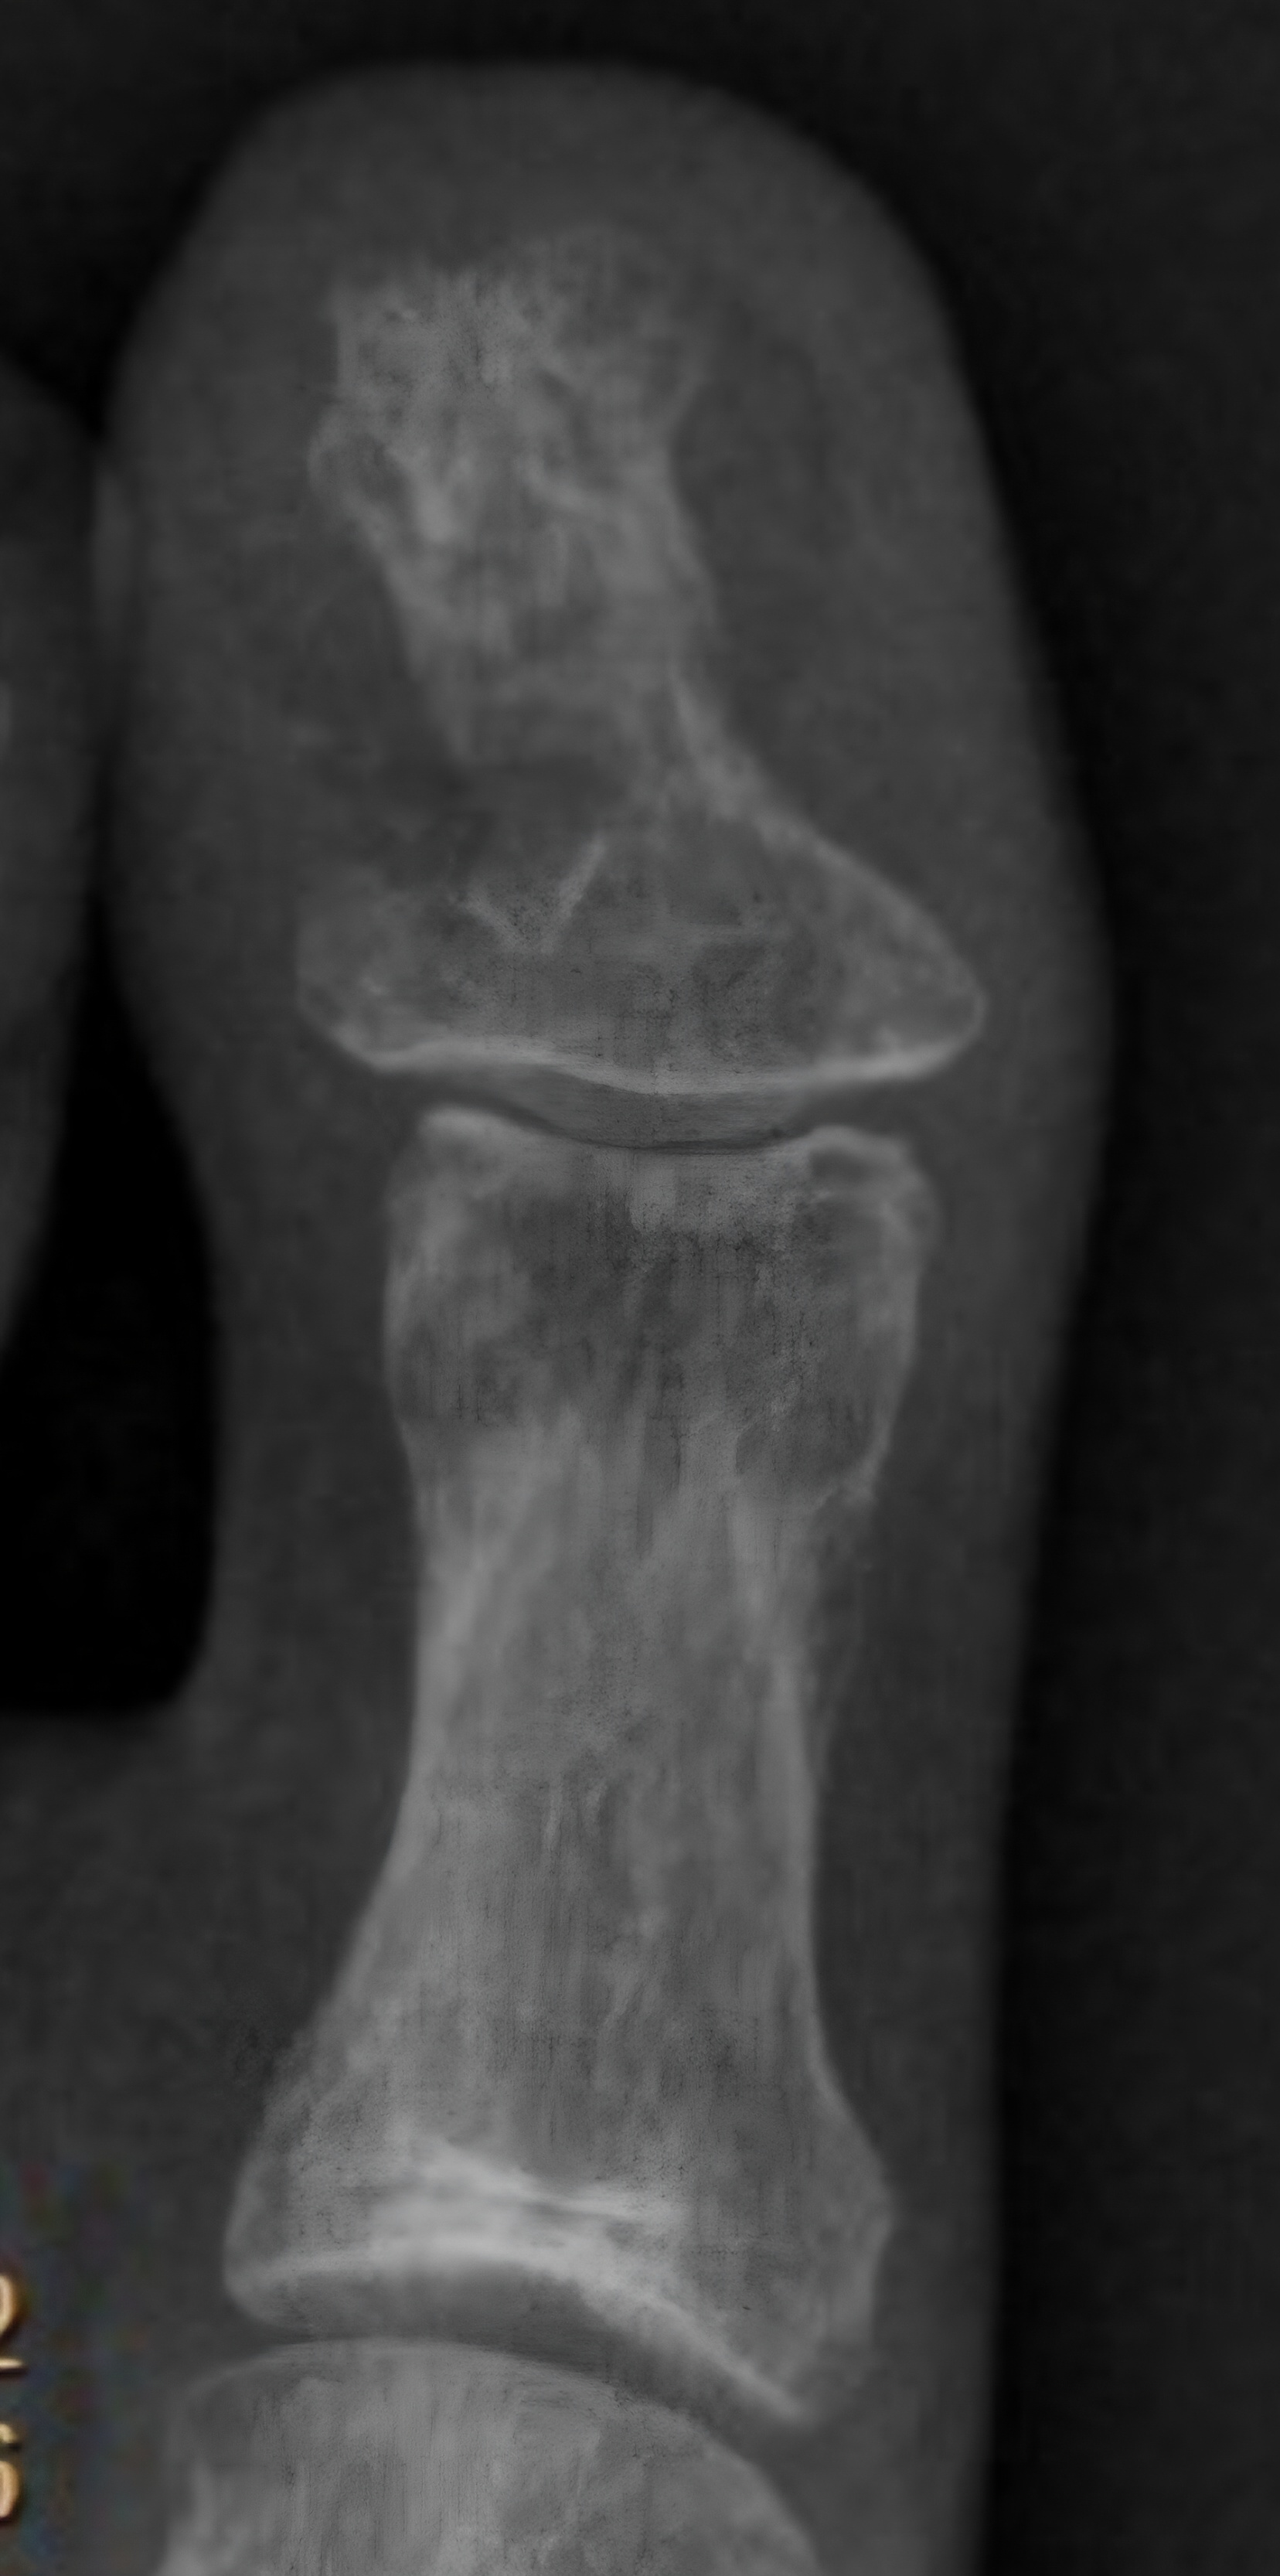

Left Great Toe 6 weeks post second bone (lateral) debridement surgery & left / right Great Toe comparisons:

Left Great Toe 12 weeks post first bone debridement surgery & left / right Great Toe comparisons:

post first bone debridement surgery (medial side)